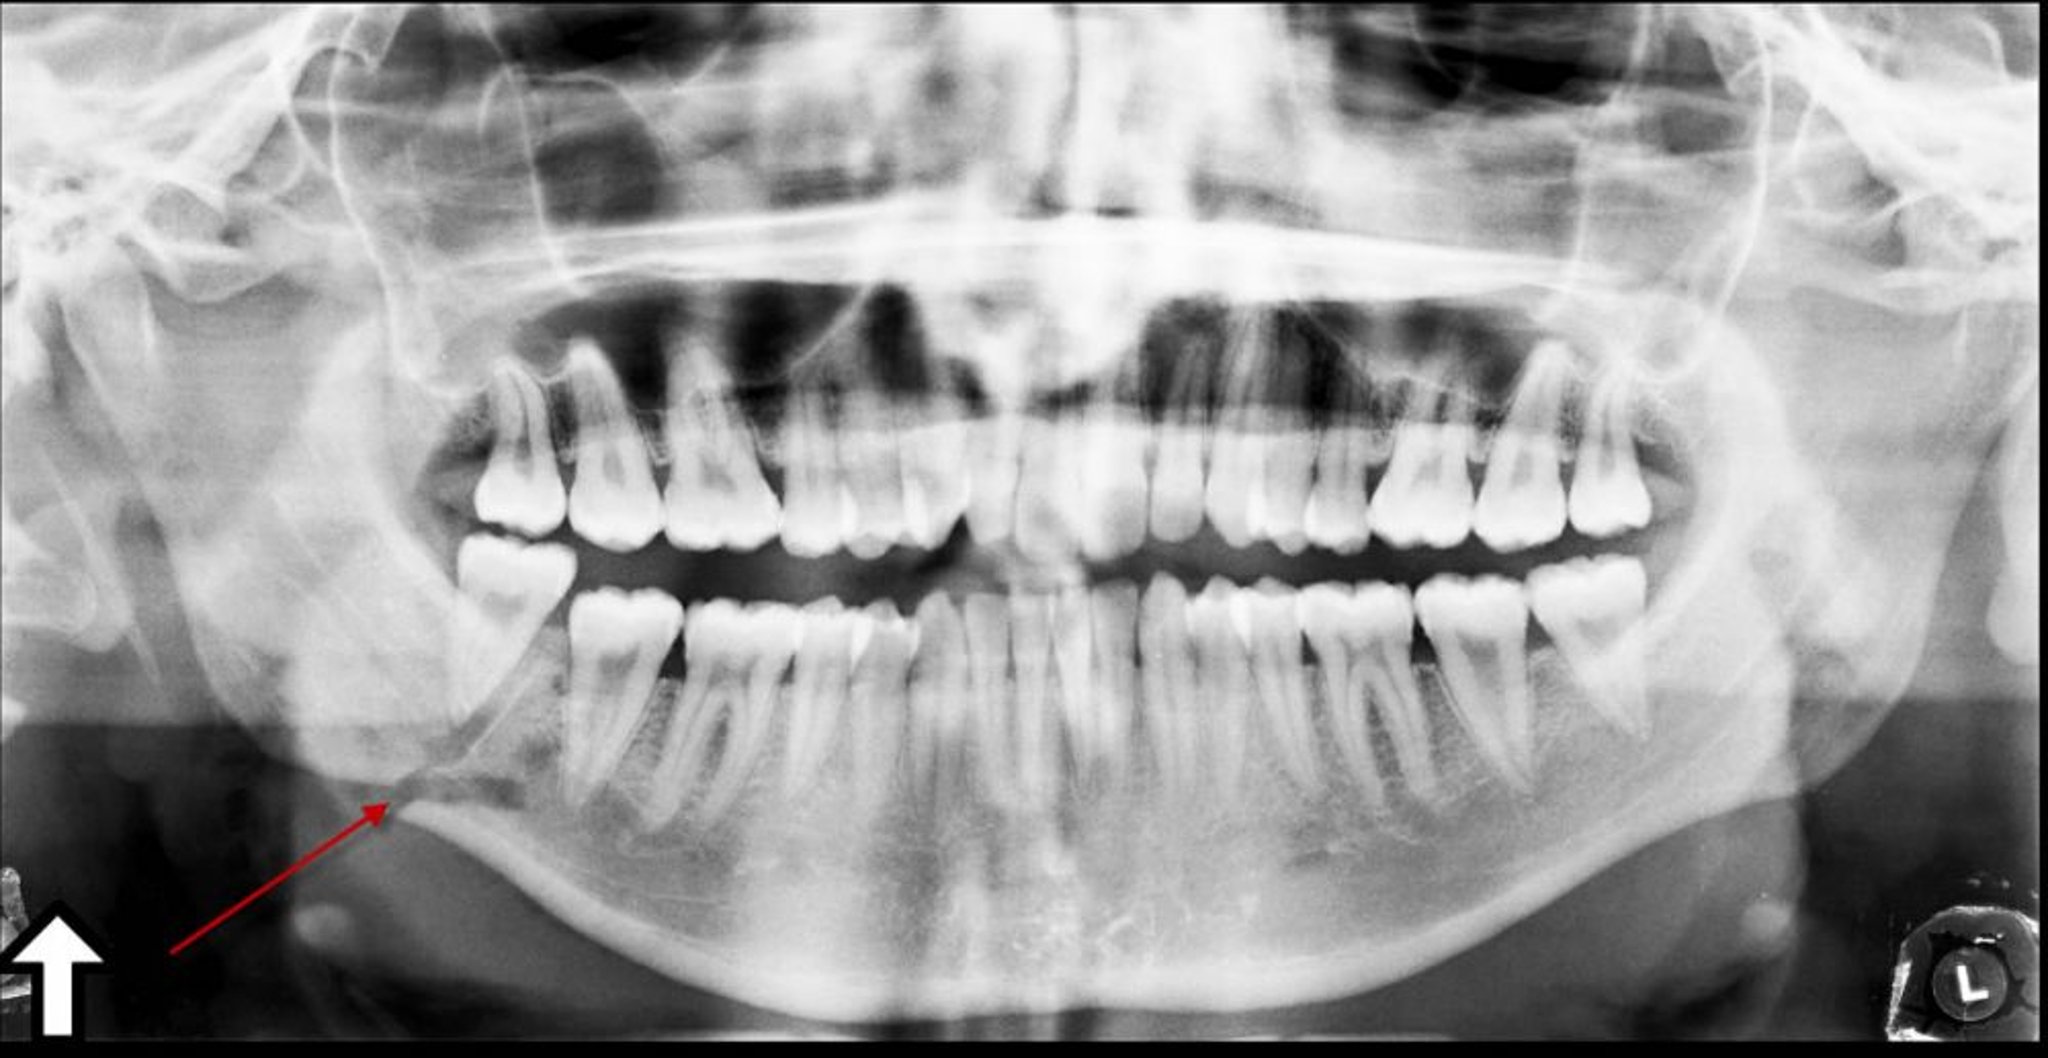

Fratura do ângulo da mandíbula

Essa radiografia panorâmica mostra translucência (seta) no ângulo da mandíbula, representando uma fratura.